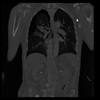

29 CUERPO,CE,Coronal,3.000,CUERPO,Coronal,